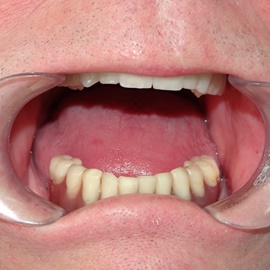

Pacjent stracił wszystkie zęby w żuchwie. Upłynęło dziesięć lat od czasu osadzenia pięciu implantów i wykonania protezy Branemarka przykręcanej do implantów. Dzięki takiemu rozwiązaniu można zdjąć protezę w gabinecie, odświeżyć, ewentualnie naprawić.